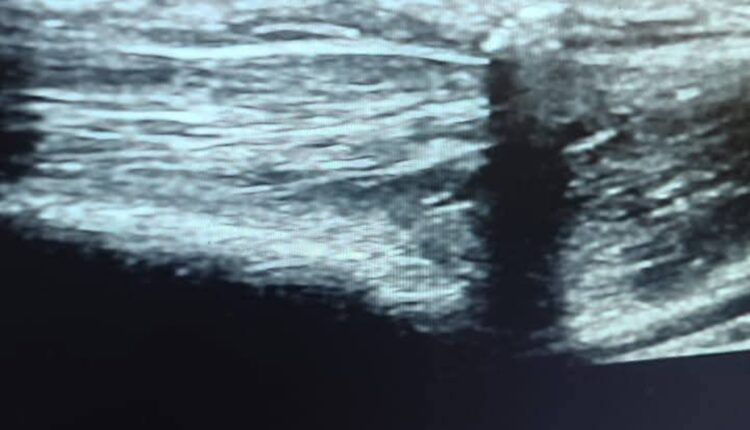

الحالة الأولى كانت لطفل يبلغ من العمر 5 سنوات، يعاني آلاما حادة في الساق اليمنى أدت إلى صعوبة في الحركة، وبعد إجراء الفحوصات اللازمة، including الأشعة التلفزيونية (السونار)، تبين وجود جسم غريب داخل أنسجة الساق.

أما الحالة الثانية لشاب يبلغ من العمر 24 عامًا، كان يعاني من تجمع السوائل في التجويف البلوري للرئة اليمنى، وقام الأطباء بإجراء عملية “بزل السائل البلوري” باستخدام توجيه الموجات فوق الصوتية، بالإضافة إلى تركيب قنية مركزية (CVP) لتسهيل العلاج، وقد تحسنت حالته الصحية بشكل ملحوظ.